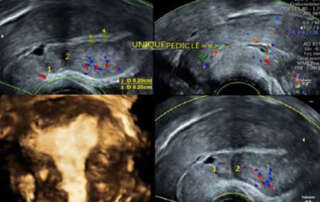

Ultrasound features of uterosacral ligaments on transvaginal scanning

DOI: 10.36205/trocar4.2022003